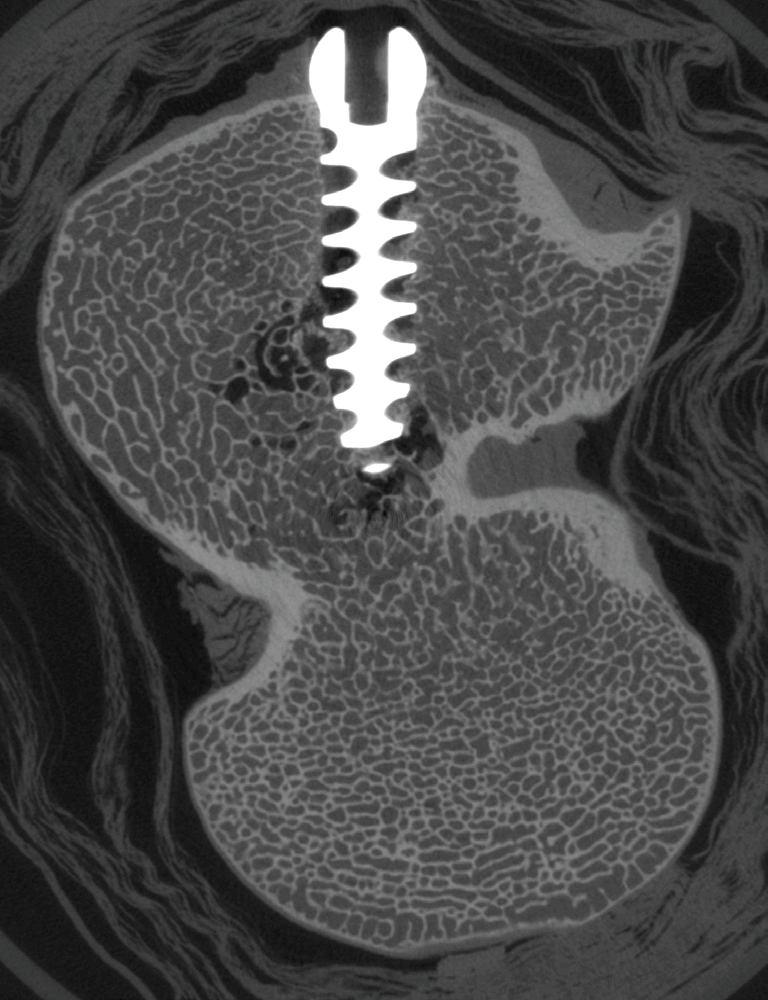

Wir haben unser Objekt mit dem X4 POSEIDON bei einer Röntgenenergie von 110 kV, einem 1 mm Molybdänfilter und einer Voxelgröße von 30 µm gescannt. Das Schnittbild durch eine Titanschraube im Kondylus des Femurs zeigt keinerlei Artefakte im Schatten des Metalls. Die unbeschädigte Knochenstruktur im Gewindegang der Schraube ist klar zu erkennen.